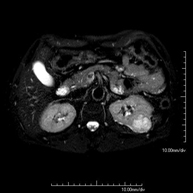

- RM d'Abdomen

Prova diagnòstica no invasiva que consisteix en l'obtenció d'imatges d'alta definició anatòmica de l'abdomen mitjançant l'ús d'un camp electromagnètic i ones de ràdio (amb un emissor i un receptor). No utilitza radiació ionitzant. En aquesta exploració s'inclouen el fetge, el pàncrees, la melsa, la via biliar, la vesícula biliar, les glàndules suprarenals, els ronyons, l'aorta abdominal, la vena cava inferior, l'estómac, el duodè, etc. En alguns casos caldrà emprar contrast paramagnètic (Gadolini) per caracteritzar les lesions. - RM Pelvis femenina